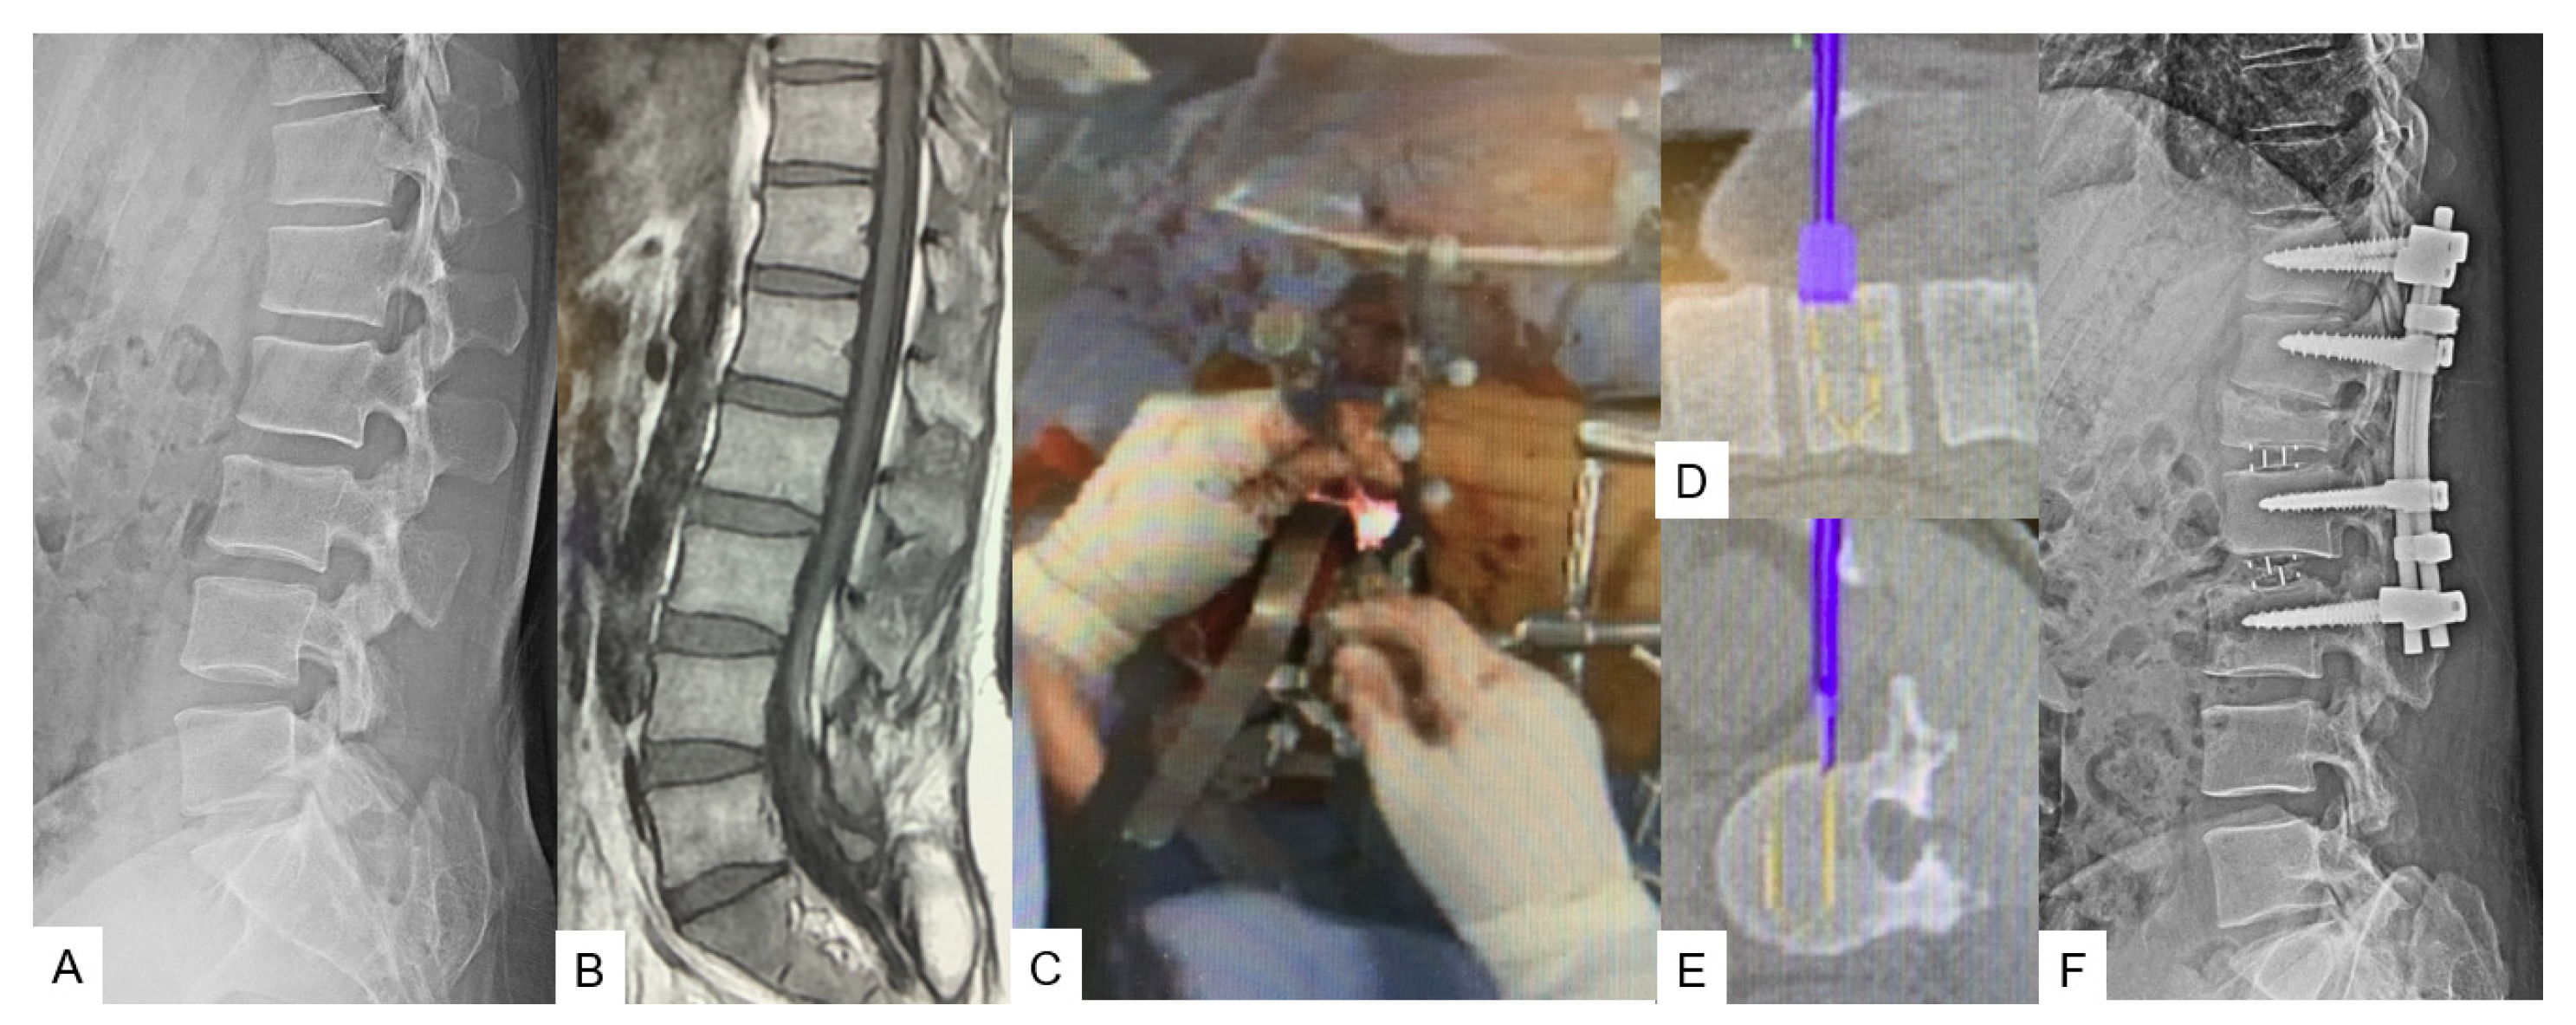

3.1. Lumbar Anterior Application

3.1.1. OLIF51 [10]

3.1.2. Lateral Osteotomy [11]